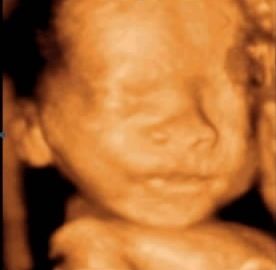

这次宝宝倒不用胳膊挡脸了,但人家小手死死拽着一条脐带往嘴里送...劝啊劝了半天才放开^_^,终于照到了正脸。

整个拍摄过程连中间出去蹓跶花了差不多两个小时,比想象的要费时费力多了(^◇^;)。但整个过程特别温馨愉快,大夫很耐心,照不好不罢休;家人在旁边七嘴八舌的讨论孩子像谁;小家伙一动,一打哈欠,大家就一阵哈哈,搞得我很有成就感^_^〜

下面秀图^_^!